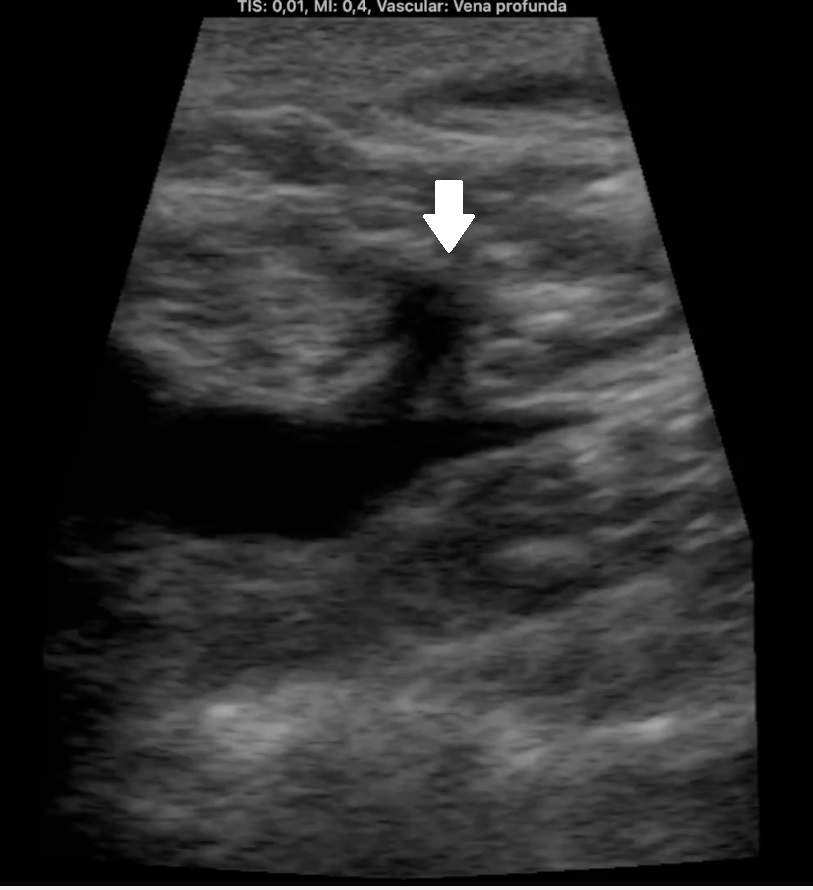

Ocupación de espacio con trombo venoso ecogénico desde poplítea hasta tercio superior, así como safenas externa e interna (imagen 2 femoral profunda e imagen 3 safena mayor). Lesión isoecogénica en segmentos hepáticos V/VI de 6,65 x 5,87 cm (imagen 4).

En urgencias hospitalarias LDH 383, FA 133, GGT 88, BT 1,21, DD 19898. Ecografía de MID realizada por cirugía vascular.

Masa hepática sospechosa de malignidad. TVP MID secundario a lo previo que se confirma por cirugía vascular. Diagnóstico diferencial con metástasis hepáticas y estirpe hepatobiliar.